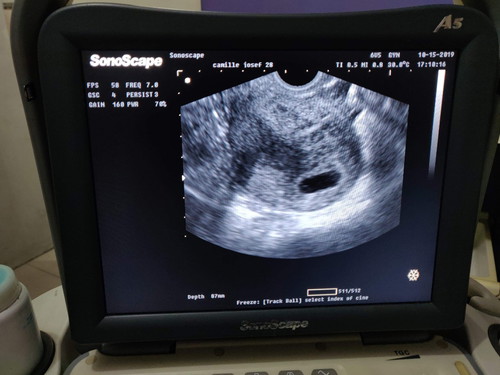

Last mens ko po Aug.10, 2019 so probably 2months pregnant po ako. pagkakita sa Trans V.Ultrasound di sya pang 2months, maliit yung tyan ko at wala pang makitang baby, sac lang ang meron, walang laman. Posible po kaya magbuntis ako ng di niregla ng matagal? sabi ng OB mga nsa 2weeks plang akong buntis kya di mkita sa ultrasound. maghintay pa ng ilang linggo at uulitin ung ultrasound. since august pa ko di na ulit nireregla. dpat 2months na sya. Bat po kaya gnun?

Baka 2weeks ka pa nga lang buntis. Possible na nadelay ka lang ng period talaga then 2weeks ago pa lang nafertilize egg mo

salamat sa sagot :) sana after 2weeks magpakita na c baby sa ultrasound. Nai stress kc ako kakaisip sa blighted ovum na ini explain ng OB, bka mabugok. pero praying kmi na magpakita na c Baby :)